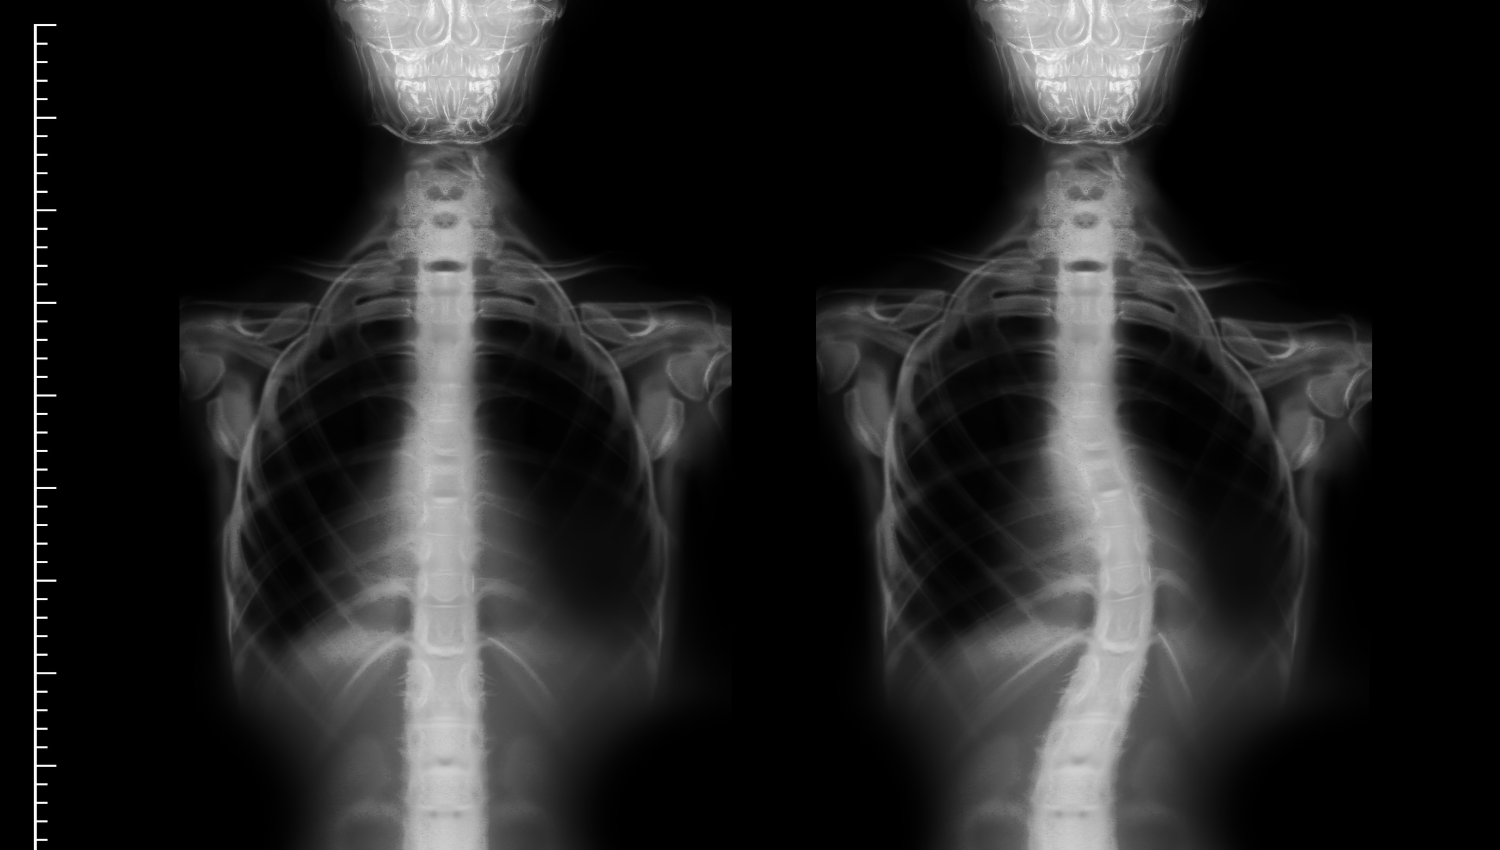

La escoliosis es una condición en la que la columna vertebral se curva anormalmente hacia un lado, formando una «C» o una «S». Aunque es más común durante la adolescencia, también puede desarrollarse en adultos debido a factores degenerativos. Si no se trata adecuadamente, la escoliosis puede causar dolor crónico, problemas de movilidad y, en casos severos, dificultades respiratorias y cardíacas